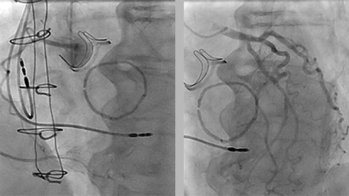

Différence entre amylose AL et ATTR, symptômes extra-cardiaques… Les signaux qui doivent conduire à suspecter une amylose revus par le Dr Antonin Trimaille et le Pr Nicolas Lamblin, dans le 1er épisode de la série “Amyloses cardiaques, les situations cliniques du cardiologue en formation”.